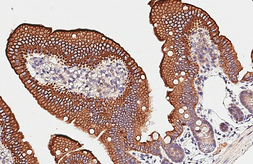

Images

Description

Applications